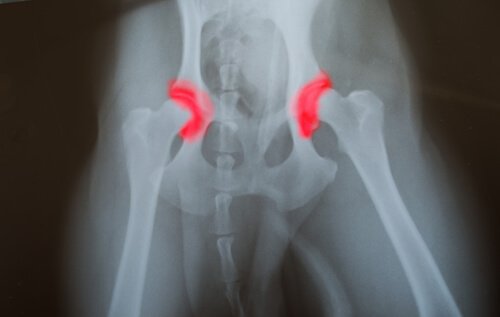

La dysplasie de la hanche ou du coude est une maladie héréditaire qui se transmet de génération en génération. Les os qui forment une articulation, ceux de la hanche ou du coude, ne sont alors pas positionnés ou alignés correctement.

Ce trouble produit alors des frottements et des mouvements inappropriés, ce qui entraine une usure accélérée qui mène à d’autres problèmes dus au mauvais fonctionnement de l’articulation. Le problème de cette maladie, c’est qu’elle est silencieuse.